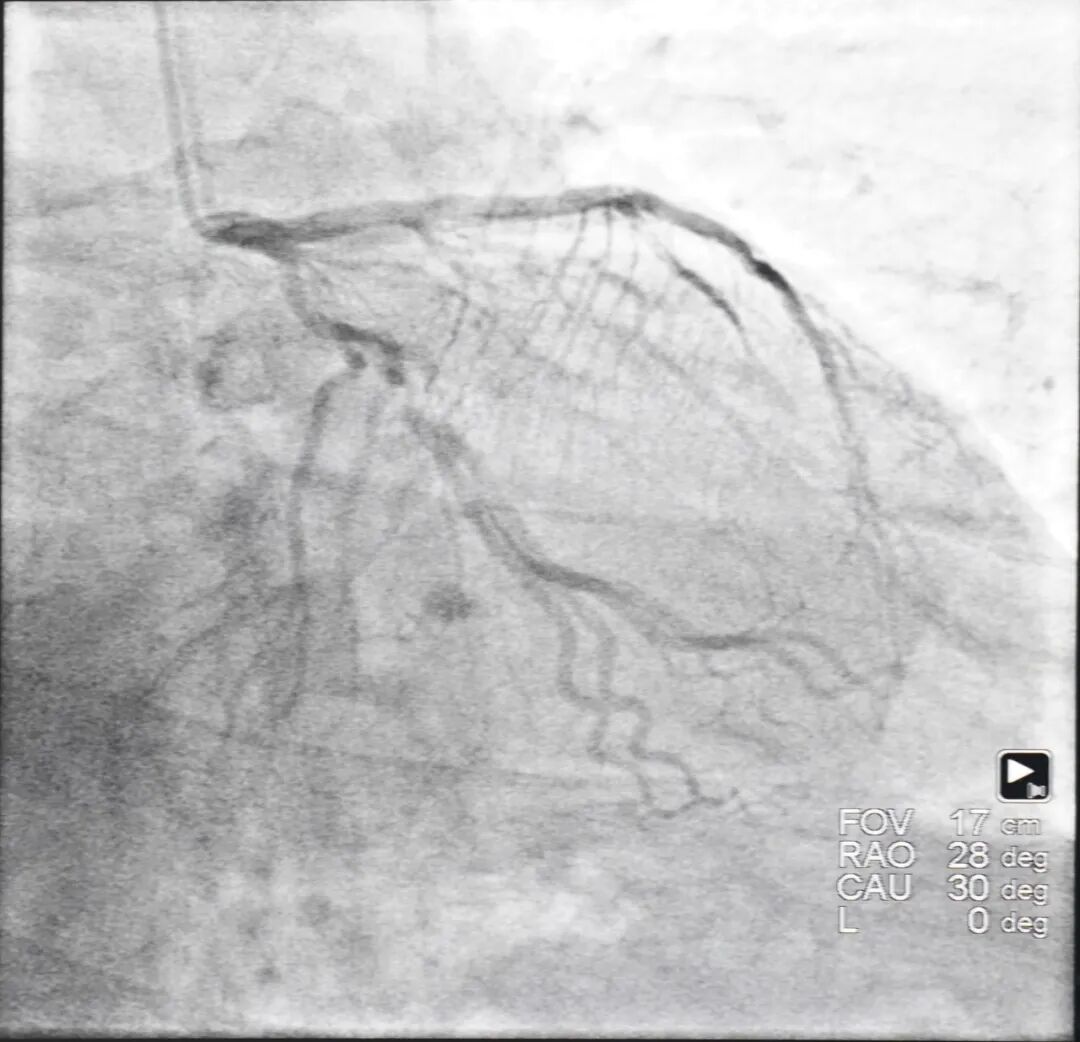

同济医院术者为曾和松教授,病例为三支病变背景下处理回旋支病变。冠脉造影提示回旋支狭窄达95%,属重度狭窄,同时合并弥漫性病变、分叉病变,且病变血管走行较迂曲。需同步实施双导丝边支保护,对操作协同、路径控制与器械递送稳定性的要求同步提升。术者操控唯迈医疗 ETcath® 血管介入手术机器人完成挂冠、双导丝分别推送至主支与分支远端、预扩、支架植入及后扩全流程,即刻造影无残余狭窄。